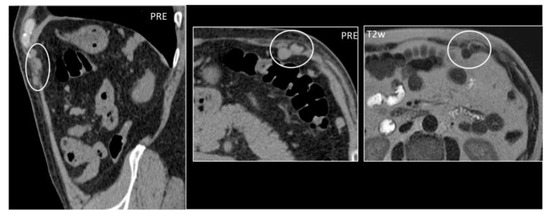

Granulomas are protective responses to destroy or sequester particles that are deemed harmful to the body, frequently seen in the context of chronic infections, inflammatory diseases, and foreign bodies. On US, retained foreign bodies are usually hyperechoic with posterior acoustic shadowing, although their appearance depends on their content [3]. As granulomas develop, they appear as well-defined nodular lesions with a peripheral hyperechoic, ill-defined halo that slowly becomes hypoechoic and then hypervascular [3,8]. CT demonstrates a soft tissue lesion with punctuate or gross calcifications, surrounded by fat stranding [5]. Slight peripheral contrast uptake is seen in chronic stages (Figure 3).

Figure 3. Granuloma occurring along a surgical mesh for an inguinal hernia repair. Axial CT on unenhanced (image on the left) and delayed phase at 10 min (image on the right) shows the formation of a nodular, fibrotic mass, with uptake contrast in delayed phases around a surgical mesh (circle).